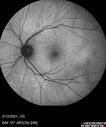

Branch Retinal Vein Occlusion with Venous Macroaneurysm (collateral)280 views66 year old female Did not notice vision loss in the right eye. The right eye has been a little worse than the left but now is much worse. Picked up during annual eye examination. VA had been 20/20 in 5 years ago.

History of brain and spinal cord radiation 1986 for T-cell lymphoma. Now with breast cancer, ablation for tachycardia, HTN

VA OD 6/200, OS 20/32Oct 16, 2021